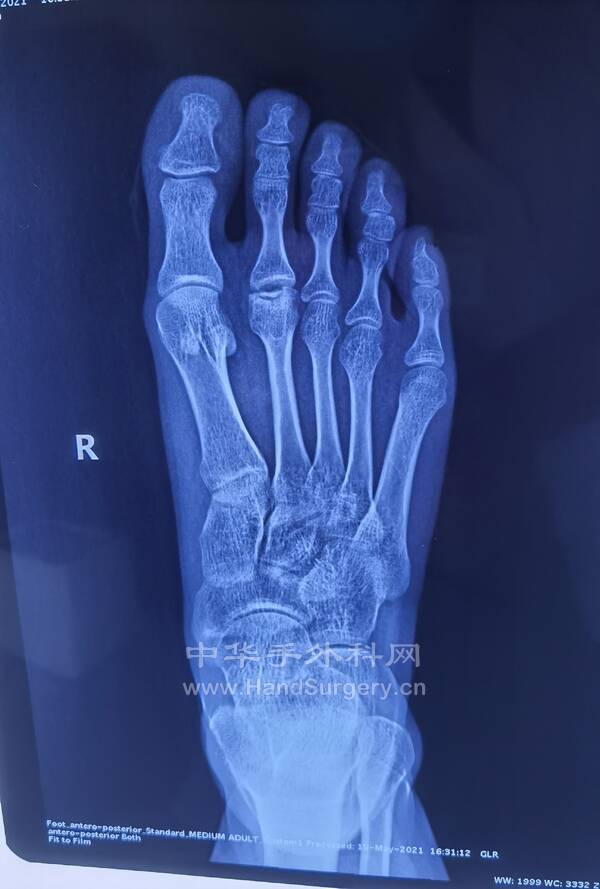

跟距骨桥,拇外翻患者行距下关节融合术,拇外翻矫形术后8周复查,